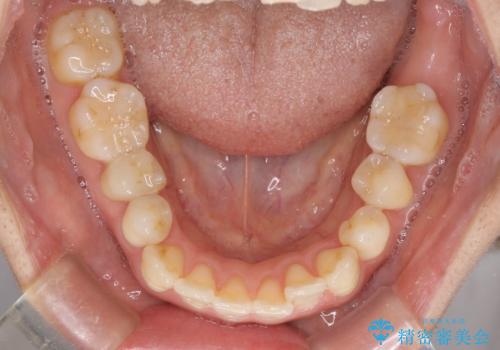

- 上下奥歯の欠損を気にして来院された患者様です。

以前矯正した後戻りにより前歯に叢生が認められたため、矯正治療の提案をしたところ、補綴治療と合わせて矯正治療を行うこととしました。

下顎欠損部はインプラントにて、上顎中間欠損部はブリッジによる補綴治療を行い、他にも気になっている銀歯をセラミックインレーやゴールドインレーにて修復治療を行うこととしました。

後戻りの程度は軽度であったため、インビザライン・ライトを用いて歯列を整えました。

再度後戻りするリスクを最小限に食い止めるため、下顎前歯の舌側を細いワイヤーで固定しました。